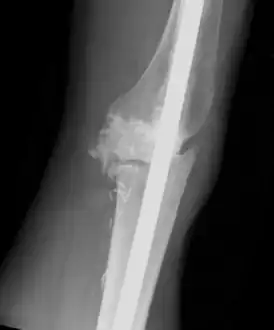

Individual with tumoral calcinosis- Lateral radiograph of the left knee demonstrating an intramedullary rod -

Oblique radiograph of the right hand demonstrating soft tissue calcification, characteristic of dialysis related metastatic calcification. -